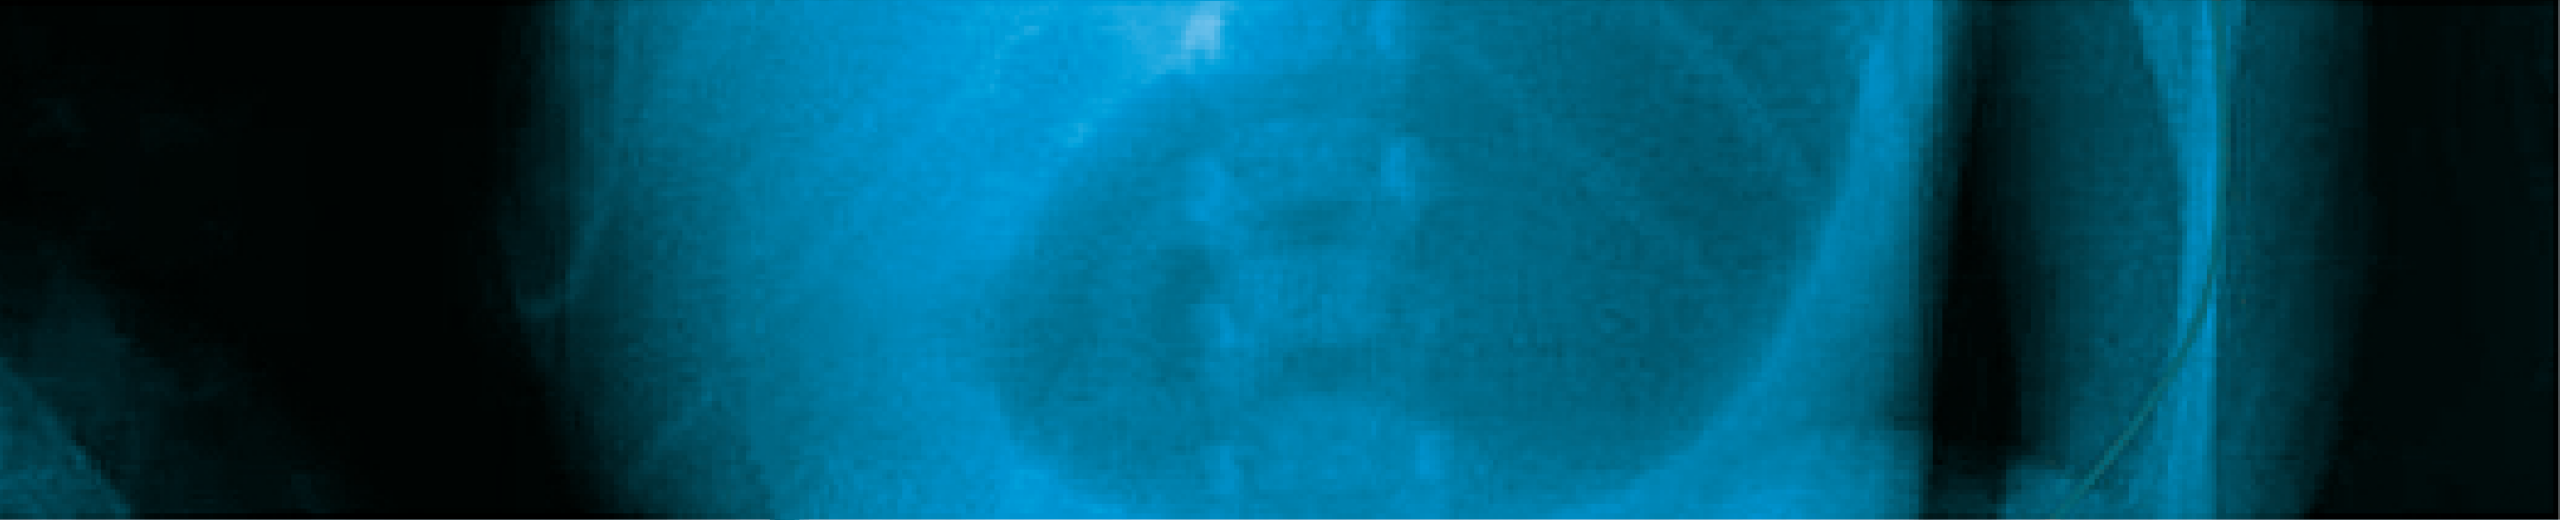

Con la sospecha clínica de estenosis hipertrófica de píloro, se solicita estudio ecosonográfico, el cual se observa en forma clara la imagen característica de la elongación del píloro, con aumento del grosor del componente muscular del píloro. El informe consta de los siguientes datos: -Hígado de ecogenicidad, forma y tamaño normal. -Vesícula biliar de paredes delgadas, sin ecos internos, no existe dilatación de vías biliares. -Riñón derecho de forma normal. -Engrosamiento de la pared muscular a nivel del píloro, que medido en el centro del canal pilórico tiene un espesor de 3.7 mm y una longitud del canal de 17 mm. -Estómago se halla distendido con contenido alimenticio y aire, retraso en el vaciamiento gástrico en el estudio dinámico.

La clínica del padecimiento conforma una tríada distintiva (vómitos postprandiales violentos, ondas peristálticas de lucha y oliva palpable) que permite el diagnóstico en el 90% de casos 1 3. La ecografía abdominal con sensibilidad de 90-99% y especificidad de 97-100%, en manos expertas, confirma el diagnóstico 1 2 3. La imagen ecosonográfica clásica es aumento del grosor de la musculatura (normal 2 mm) y alargamiento del canal pilórico (normal 12 mm) 1 4 5 6. El uso de bario para un estudio de contraste, la endoscopía digestiva alta, son posibilidades para determinados casos 4 6. El laboratorio, en algunos casos, determinará una alcalosis metabólica hipoclorémica hipokalémica, resultado de la pérdida de cloro en los vómitos y aumento de la concentración de bicarbonato; y la consecuente retención de hidrogeniones por el riñón en detrimento del potasio 1 3 7. Es posible el aumento de la bilirrubina indirecta por disminución del paso del estómago al duodeno, con incremento de la circulación enterohepática.